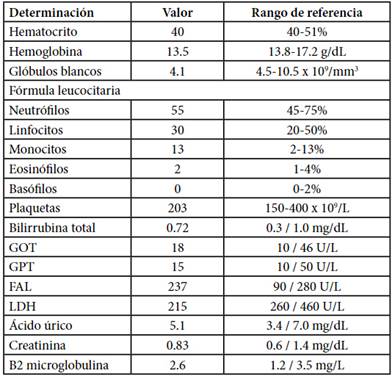

En el laboratorio se constataba anemia leve, el resto del hemograma era normal como así también la LDH y el resto de la química. Las serologías virales fueron negativas (Tabla 1).

Tabla 1. Laboratorio al ingreso